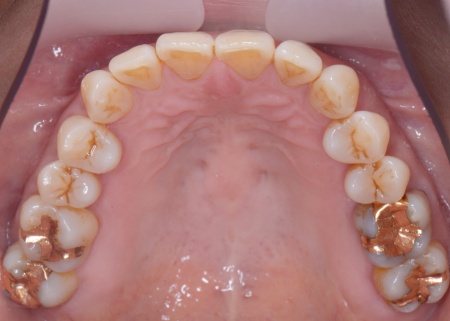

| カウンセリング | 拝見したところ、上下左右の奥歯計8本(第1大臼歯、第2大臼歯)に重度の歯周病が認められました。 歯周病は歯を支えている骨や歯ぐきに炎症が起こる病気です。進行すると歯がぐらついたり、噛む力が弱くなったりします。 さらに悪化すると歯を失う可能性が高くなるだけでなく、周囲の歯にも影響が広がることがあります。 特に下の奥歯2本(左右第1大臼歯)は歯を支えている骨が著しく減少して歯が大きく揺れており、治療して温存することは難しい状態でした。 また、左上の奥歯(第1大臼歯)は過去に詰め物で治療されていましたが、その下で虫歯が再発しています。 以上のことから、下左右の第1大臼歯は抜歯後に歯を補う治療、その他奥歯の治療、再発した虫歯の治療が必要と診断しました。 |

さらに虫歯が再発していた左上奥歯については、虫歯をしっかりと取り除いたうえで被せ物による修復治療を提案しました。 それぞれのメリット・デメリットを丁寧に説明したところ、治療計画に同意いただきました。 まず、歯周基本治療から開始しました。 下左右の第1大臼歯を抜歯し、その部位にインプラントを埋め込む手術を行いました。同時に、インプラントの隣にある下の第2大臼歯に対して歯周組織再生療法を施しています。 また、左上の奥歯は虫歯を取り除いたあと、歯の形を整えて型取りを行い、最終的にジルコニアクラウンを装着しています。 段階的に治療を進め、すべての治療を終了しました。 |